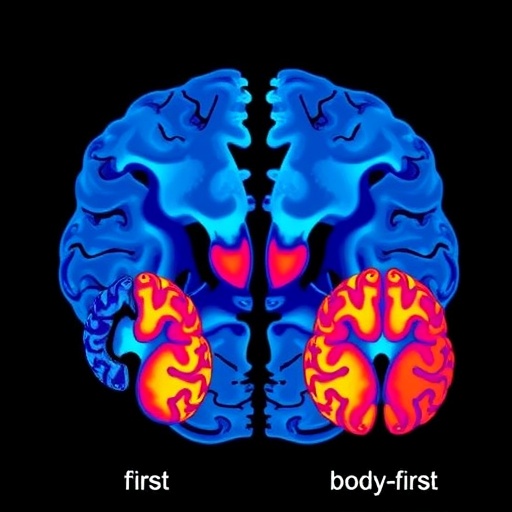

Using high-resolution MRI modalities, including both structural and functional imaging, the research team meticulously analyzed axial brain asymmetries—the differences between corresponding regions in the left and right hemispheres—among patients classified into brain-first and body-first Parkinson’s disease subtypes. The brain-first subtype is characterized by initial neurodegeneration originating within the central nervous system, whereas the body-first subtype suggests a peripheral origin with retrograde propagation toward the brain.

The investigators applied advanced neuroimaging protocols to quantify differences in cortical thickness, subcortical volume, and resting-state functional connectivity. Their findings revealed pronounced lateralization patterns in critical regions implicated in Parkinson’s pathology, such as the substantia nigra, striatum, and various cortical motor and sensory areas. Notably, the brain-first subtype exhibited more pronounced asymmetry in the substantia nigra’s structural integrity, correlating with the typically unilateral initial motor deficits observed in these patients.

Simultaneously, functional MRI analyses exposed divergent patterns of network connectivity. Brain-first patients showed disrupted coupling between the basal ganglia and motor cortex predominantly on the affected side, aligning with the hypothesis that dopaminergic neuronal loss in these areas precipitates motor symptom onset. Conversely, individuals with body-first Parkinson’s displayed more symmetric but globally altered connectivity profiles, potentially reflecting the systemic and multisite progression of alpha-synuclein pathology inherent to their subtype.

The research also contributes to ongoing debates regarding the initiation and propagation of alpha-synuclein pathology in PD. The brain-first subtype’s pronounced unilateral nigral degeneration supports models where initial CNS involvement drives disease onset. Conversely, the body-first subtype’s symmetrical connectivity disruptions lend credence to peripheral origins with systemic impact. These insights refine conceptual frameworks and may guide future neuropathological and biomarker investigations.